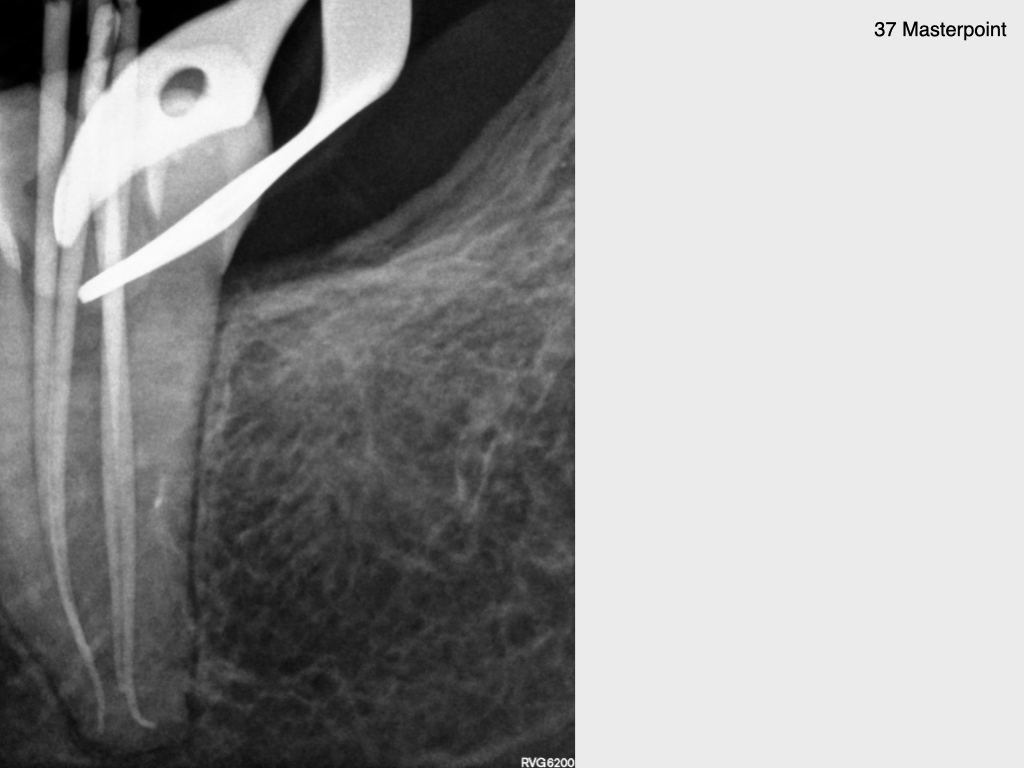

Krampf und Kampf